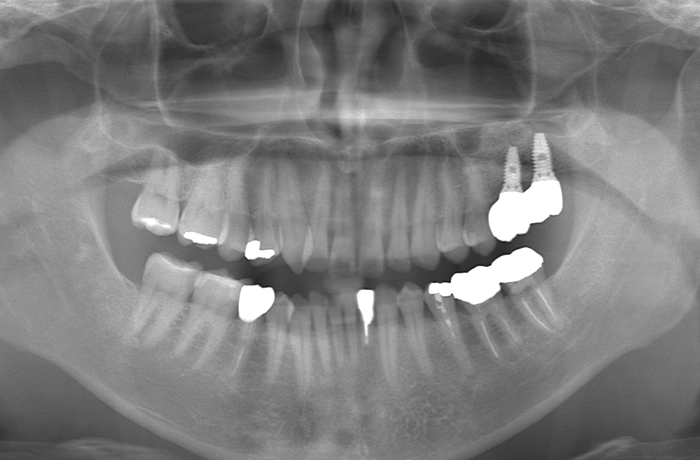

治療後

治療終了後の完成した口腔内と

レントゲン写真

サイナスリフト部の骨再生は良好で、インプラントの安定性も高く、骨吸収や透過像はありませんでした。

最終補綴装着後は咬合バランスが改善し、良好な咀嚼機能が回復。審美性にも優れ、患者様にもご満足いただけました。